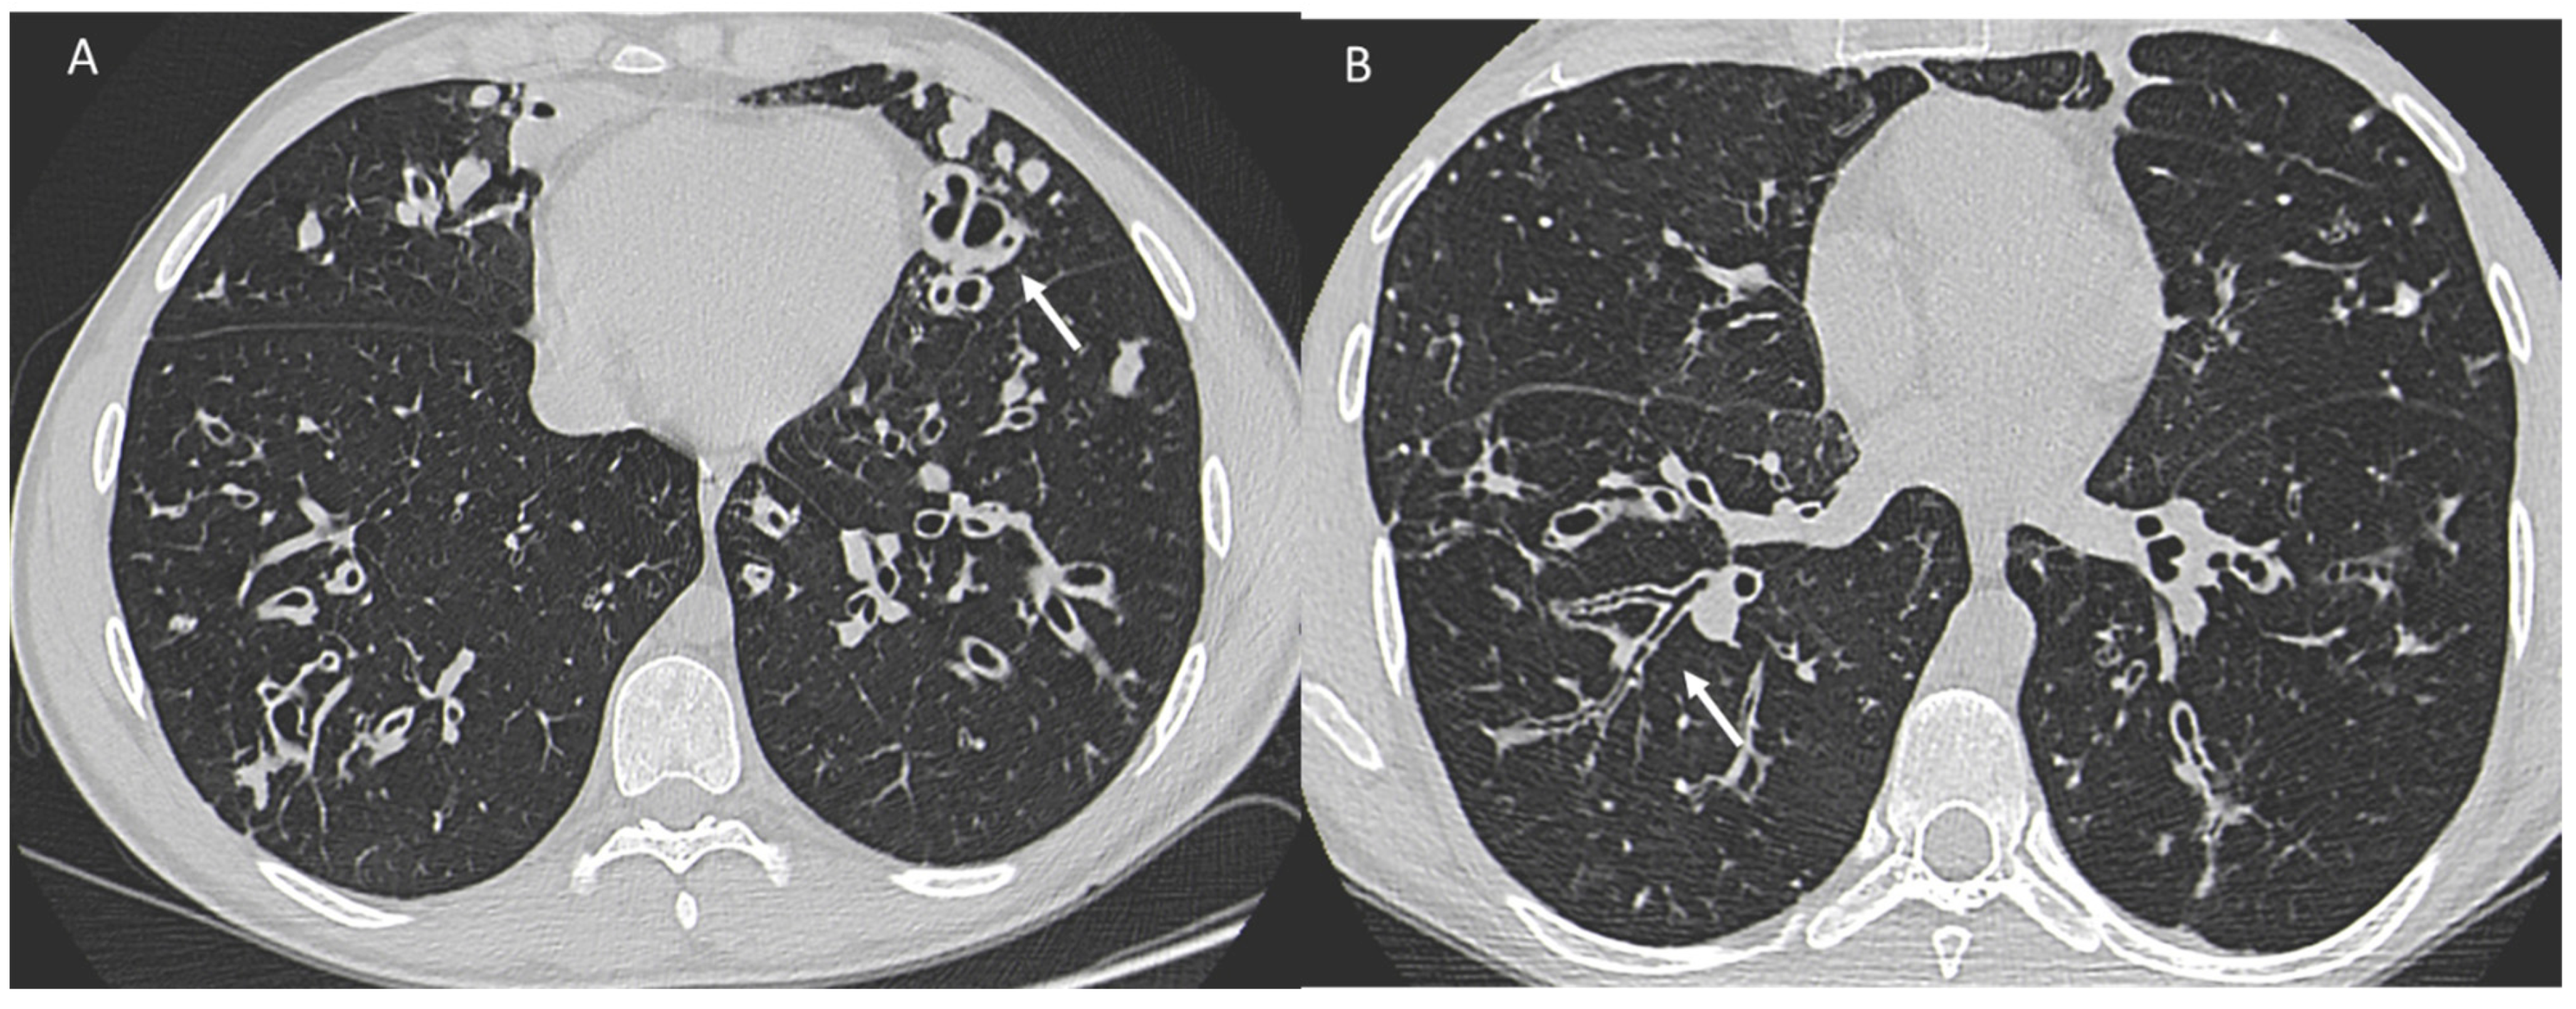

One study [103] investigated the survival of women with CF compared with men and showed that survival in the female population with CF is lower than that of men by about 5 years. Underlying this discrepancy is a different and higher anatomic-structural involvement on high-resolution chest CT (HRCT) in women with CF compared with men (Figure 3). Indeed, higher scores were recorded in women regarding the extent of bronchiectasis, involvement of bronchial branches, and severity of bronchiectasis, thus illustrating a virtually generalized involvement of the bronchial tree, as well as regarding air entrapment. This resulted in more frequent exacerbations, worse functional and nutritional outcomes, deterioration of quality of life, and greater structural damage in the female population.

Figure 3.

A woman and a man with CF with different and higher anatomo-structural involvement at HRCT in women with CF compared with men. (A) Diffuse cystic-varicoid bronchiectasis, with diffuse wall thickening and mucous plug (white arrow) in a young woman patient with cystic fibrosis. (B) Bronchiectasis with thickened walls (white arrow), especially in the medium-lower pulmonary lobes in a male patient with cystic fibrosis.